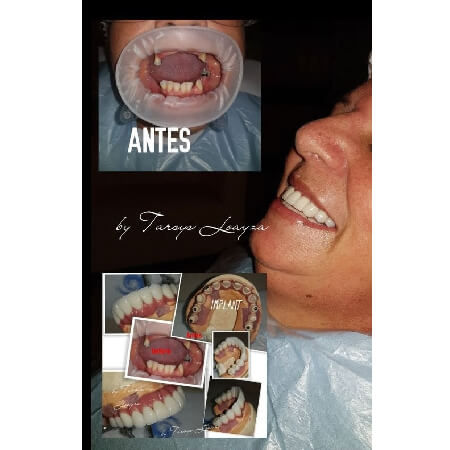

Galería de antes y después